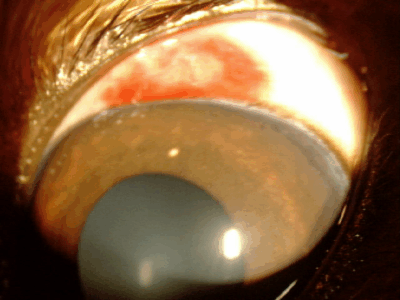

強膜充血

結膜の下の強膜血管が怒張し赤く見えます。結膜充血よりもやや太い血管が浮きでできます。原因としては、眼内の炎症(ぶどう膜炎)、緑内障などでみられます。